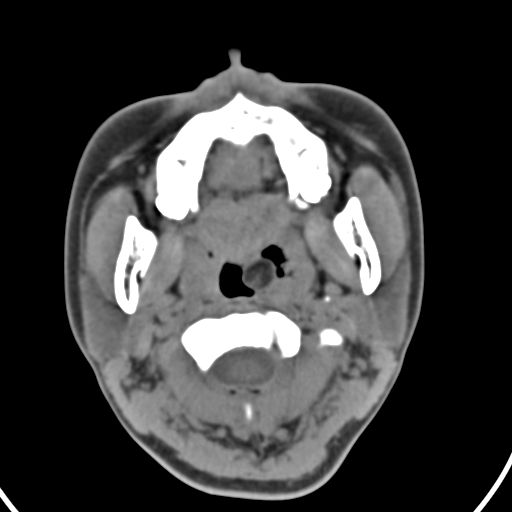

以下是引用zjzjr在2008-12-5 11:46:00的发言:[br]脂肪密度,壁有钙化.考虑口咽部皮样囊肿可能性大.双侧上颌窦炎,双侧下鼻甲粘膜肥厚.增殖腺肥大,扁桃体亦增大,考虑炎性.

以下是引用随光逐影在2008-12-5 18:27:00的发言:[br]1)考虑左侧茎突过长综合征并茎突舌骨韧带囊肿形成突入咽部;左侧咽部慢性炎症。2)鼻咽腺样体肥大。3)双侧扁桃体肿大。4)双侧上颌窦炎。5)双侧下鼻甲粘膜肥厚。